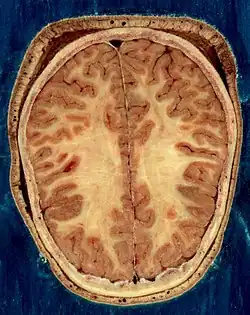

O cérebro, o tronco cerebral, o cerebelo e a medula espinhal são cobertos por três membranas chamadas meninges. As membranas são a dura-máter resistente; a aracnóide e a pia-máter interna, mais delicada. Entre a aracnoide e a pia-máter estão o espaço e as cisternas subaracnoides, que contêm o líquido cefalorraquidiano.[10] A membrana mais externa do córtex cerebral é a membrana basal da pia-máter e é uma parte importante da barreira hematoencefálica.[11] O cérebro vivo é muito macio, tendo uma consistência de gel semelhante ao tofu.[12] As camadas corticais de neurônios constituem grande parte da matéria cinzenta cerebral, enquanto as regiões subcorticais mais profundas dos axônios mielinizados constituem a matéria branca.[6] A substância branca do cérebro representa cerca de metade do volume total do cérebro.[13]

A parte externa do cérebro é o córtex cerebral, composto de matéria cinzenta organizada em camadas. Tem 2 a 4 milímetros de espessura e é profundamente dobrado para dar uma aparência complicada.[18] Abaixo do córtex está a matéria branca cerebral. A maior parte do córtex cerebral é o neocórtex, que possui seis camadas neuronais. O resto do córtex é de alocórtex, que tem três ou quatro camadas.[19]